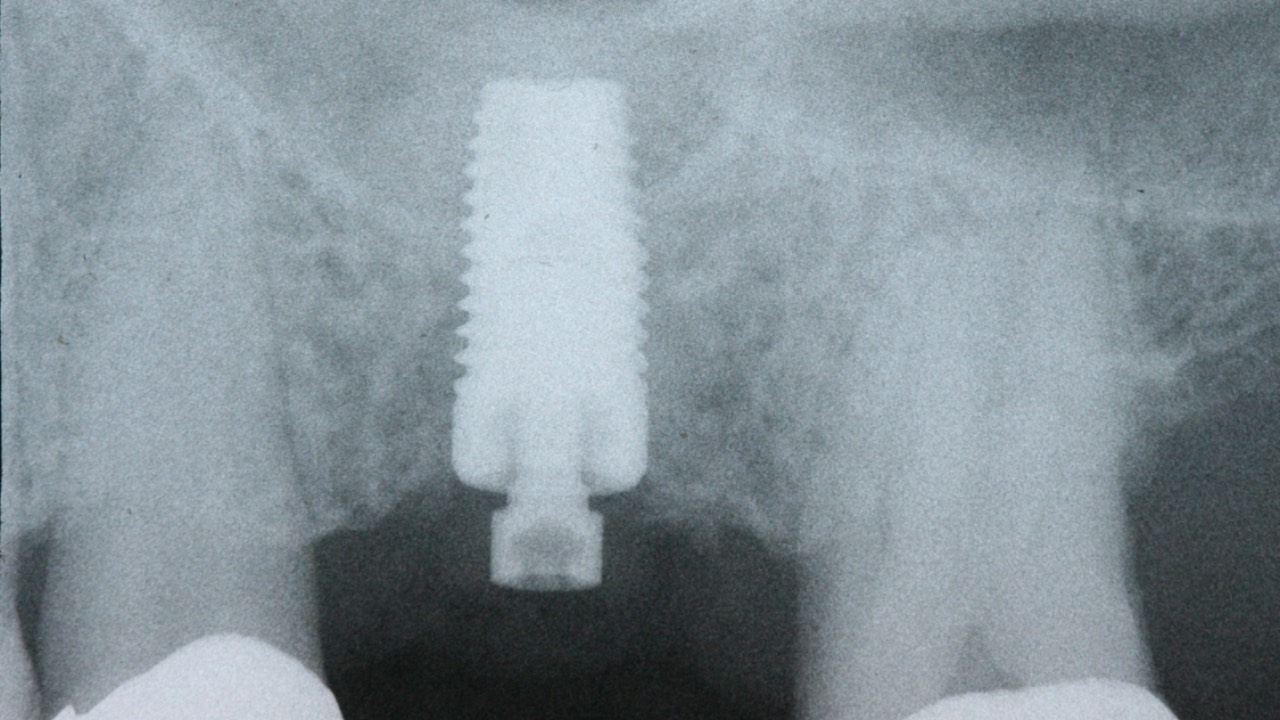

- Surgical Techniques in Implant Placement